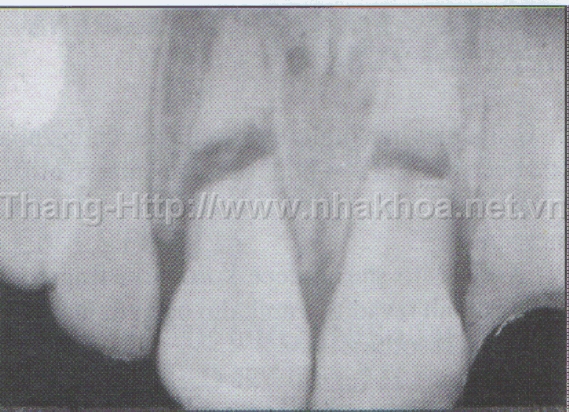

Gãy thân răng, gãy gần cổ răng dưới nướu

Phần gãy thân răng nên nhổ bỏ, lấy tủy phần chân răng và tạo cùi giả thường làm bằng chốt đúc sau đó gắn mão phục hình trên chân răng. Để phòng ngừa chấn thương răng, cần mang khí cụ bảo vệ hàm mặt khi tham dự thể thao; đội mũ bảo hiểm có cằm khi ngồi xe mô tô tham gia giao thông; thắt dây an toàn khi ngồi trong xe hơi. Nên chỉnh nha cho trẻ trong các trường hợp sâu, hô để tránh tổn thương vùng răng cửa khi ngã. Khi có tổn thương ở răng, nên sớm đến trung tâm điều trị nha khoa.